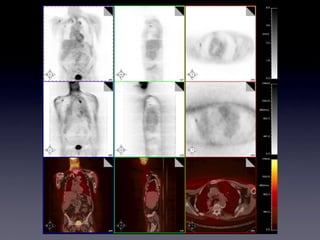

The sculpture "The Short, Rich Life of Positronium" commemorates fundamental research on antimatter conducted at the University of Michigan. Positron emission tomography (PET) uses positron-emitting radioactive isotopes as tracers and coincidence detection of the resulting back-to-back photons to construct tomographic images. PET enables visualization of functional processes in the body by tracking radioactive tracers like fluorodeoxyglucose, which is used to show glucose metabolism and thus tissue activity. While providing valuable medical information, PET also involves some radiation risks due to the penetrating nature of the emitted photons.